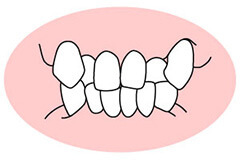

改善が必要な歯並び

叢生